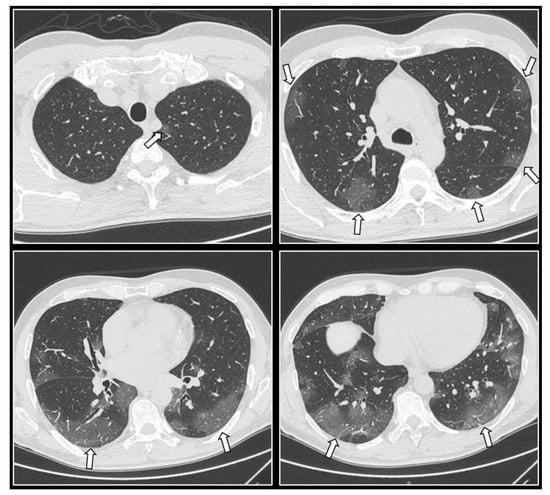

2.3.4. CT Imaging Findings